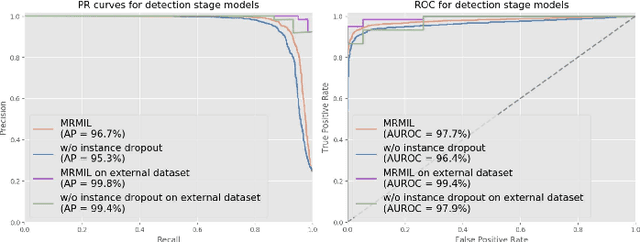

Histopathological images provide rich information for disease diagnosis. Large numbers of histopathological images have been digitized into high resolution whole slide images, opening opportunities in developing computational image analysis tools to reduce pathologists' workload and potentially improve inter- and intra- observer agreement. Most previous work on whole slide image analysis has focused on classification or segmentation of small pre-selected regions-of-interest, which requires fine-grained annotation and is non-trivial to extend for large-scale whole slide analysis. In this paper, we proposed a multi-resolution multiple instance learning model that leverages saliency maps to detect suspicious regions for fine-grained grade prediction. Instead of relying on expensive region- or pixel-level annotations, our model can be trained end-to-end with only slide-level labels. The model is developed on a large-scale prostate biopsy dataset containing 20,229 slides from 830 patients. The model achieved 92.7% accuracy, 81.8% Cohen's Kappa for benign, low grade (i.e. Grade group 1) and high grade (i.e. Grade group >= 2) prediction, an area under the receiver operating characteristic curve (AUROC) of 98.2% and an average precision (AP) of 97.4% for differentiating malignant and benign slides. The model obtained an AUROC of 99.4% and an AP of 99.8% for cancer detection on an external dataset.